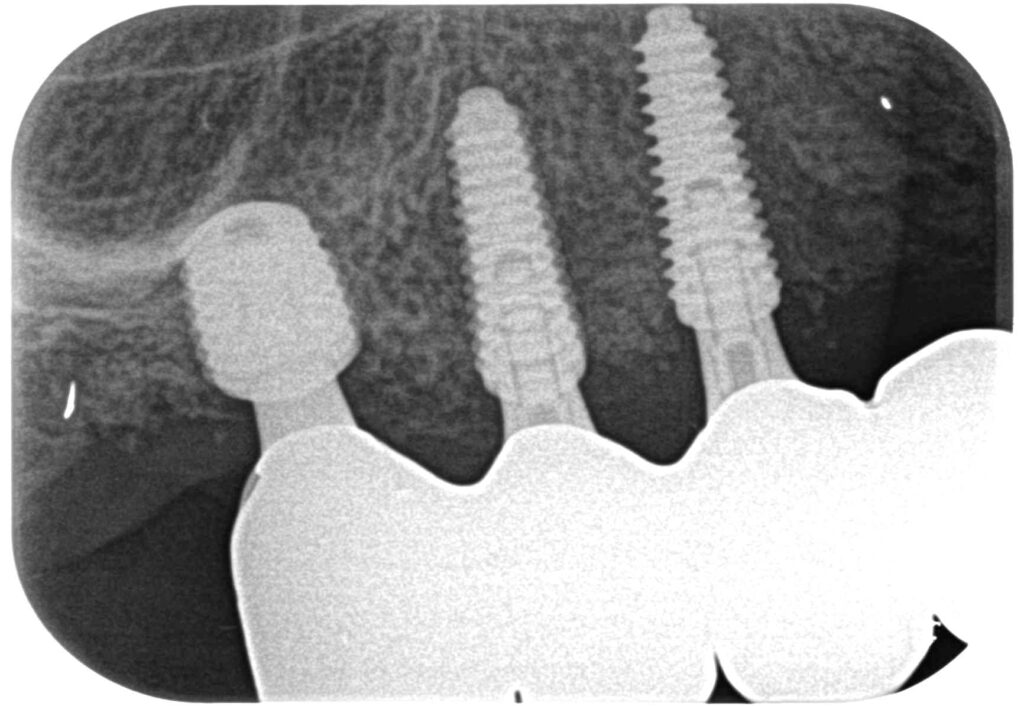

症例544歳男性 右上奥歯がない為噛めない 入れ歯は入れたくない

治療前

治療後

治療前

治療後

残存骨の高さが1~2mmしかない為、ソケットリフト(上顎洞洞底膜挙上術)を適用。

骨の高さを確保し、インプラントを埋入。

約4ヶ月の免荷期間を経て、ジルコニアを装着。

リスクとしては外科的侵襲がある。デメリットは、保険外診療の為、経済的負担がある。

費用 64万(税込)(オペ・仮歯・最終補綴まで含む)